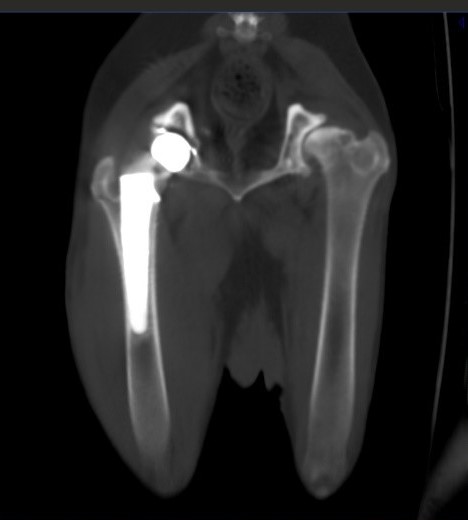

Для обеспечения успешного хирургического вмешательства необходимо провести тщательное предоперационное обследование пациента с целью выявления возможных неврологических и ортопедических патологий.Клинические признаки таких патологий могут включать боль при манипуляциях с тазобедренным суставом, особенно при его разгибании, снижение амплитуды движений, крепитацию и атрофию мышц тазовой конечности (фото 3).

При остеоартрите объективным доказательством наличия хронической боли может служить снижение мышечной массы больной конечности (фото 4). При односторонних состояниях это можно проверить посредством ее сравнения с мышечной массой здоровой конечности. В билатеральных случаях, например при дисплазии тазобедренных суставов, наблюдается общее снижение мышечного тонуса в мышцах тазовых конечностей6.

Рентгенологически степень тяжести остеоартрита можно оценить по степени выраженности склероза субхондральной кости, инконгруэнтности суставных поверхностей, а также по количеству периартикулярных остеофитов и уменьшению суставного пространства, что свидетельствует о потере хрящевого слоя5. При прогрессировании остеоартрита развивается снижение плотности костных структур из-за неиспользования больной конечности. В тяжелых случаях остеоартрита может возникнуть анкилоз пораженного сустава.